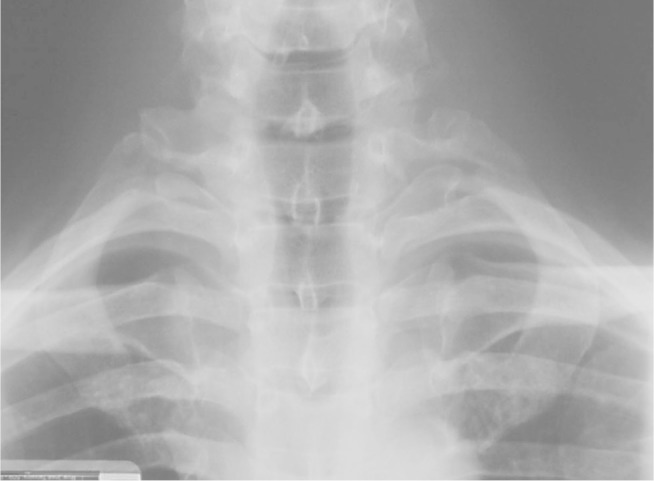

Forty-eight hours after the accident, he complained about pain in the right scapular region, which led him to undergo radiological investigation of the chest and neck, which showed bilateral fracturing of the first rib. The radiological evaluation consisted of anteroposterior (AP) and lateral radiographs of the chest, and AP and right and left lateral and anterior oblique radiographs of the cervical column. The fractures were seen on the AP radiographs (Figure 1) and shown best on the oblique projections of the neck (Figure 2). On the left side, avulsion of the transverse apophysis was associated with the fracturing of the first rib (Figures 3 and 4). Both the fractures were on the posterior part of the rib body.

Figure 1.

Radiograph in AP view showing the fractures in the posterior arch of the first ribs and the avulsion of the left transverse apophysis, shown in detail in Figure 2